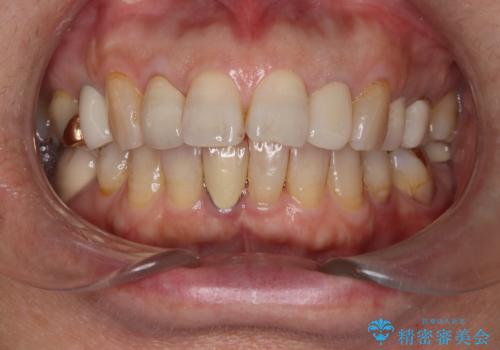

セラミッククラウン作成の為のオフィスホワイトニング

- セラミックの治療にあたりご自身の歯の色を明るくしたいとの希望でオフィスホワイトニングの施術をしました。

ご自身の歯が白く変わったので、その後のセラミック治療にも明るく白いセラミックにできると喜んでいただけました。